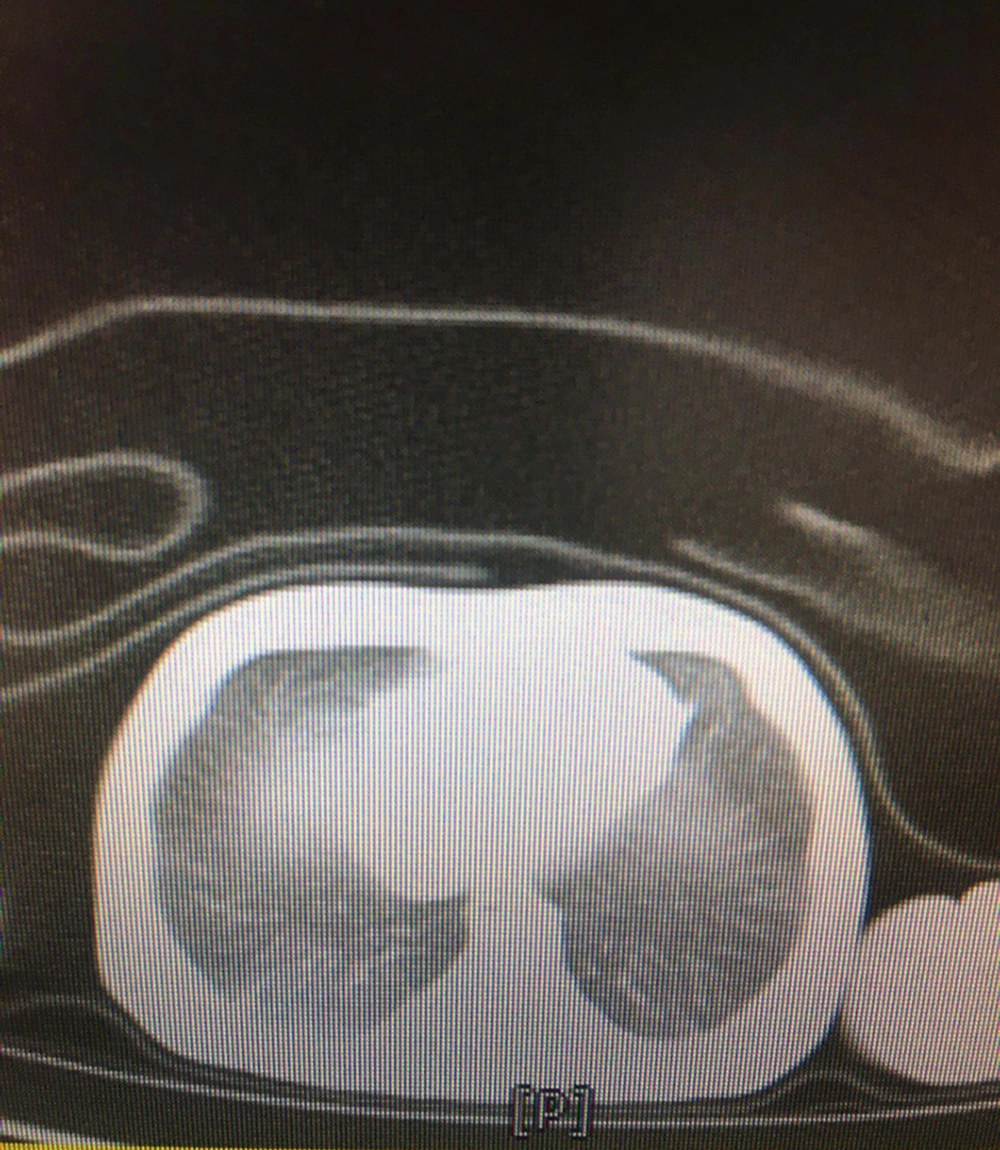

The most common clinical manifestations were respiratory distress (77.7%), followed by fever or hypothermia (18.5%), gastrointestinal problems (14.8%), and neurologic findings (3.7%). Among them, four neonates were found with a combination of symptoms. The demographic and clinical characteristics of the neonates are presented in Table 2. Few abnormalities were seen in laboratory findings. The C-reactive protein was increased in 10 (22.7%) neonates, with 3/27 (11.1%) having coagulative disorders. Lactate dehydrogenase was elevated in 12 out of 16 (75%) neonates. Besides, aspartate aminotransferase was increased in five out of 12 (41.6%) newborns, and 16/22 (72.7%) neonates had pathologic hyperbilirubinemia that was managed according to their hour-specific age. None of the neonates had leukocytosis or leukopenia, lymphopenia, thrombocytosis, or thrombocytopenia. All the cultures were negative. The chest X-rays were abnormal in 6/27 (22.2%) neonates, including ground-glass opacities (18.5%) and bilateral consolidations (3.7%). A lung CT scan was done for one of the neonates with respiratory symptoms, who had three negative RT-PCR tests but was highly suspicious of COVID-19 pneumonia. The pattern was suggestive of COVID-19 pneumonia reported by the consultant radiologist (Figure 1).

Moreover, the majority of the lung images were normal in our study, but the most common abnormalities were ground-glass opacities in 18.5% and bilateral consolidation in 3.7% of the newborn infants, respectively. Positive findings in chest X-rays have been described in 56% of neonates as the ground-glass appearance in 28% of cases (26). In a systematic review among 68 neonates, 26.5% of babies showed radiologic signs of pneumonia (5). Other radiologic findings, including increased lung marking, thickened texture, or high-density nodular shadow, have been reported in SARS-CoV-2-positive newborns. It seems that radiological features in neonates are similar to those of older children and adults (27).